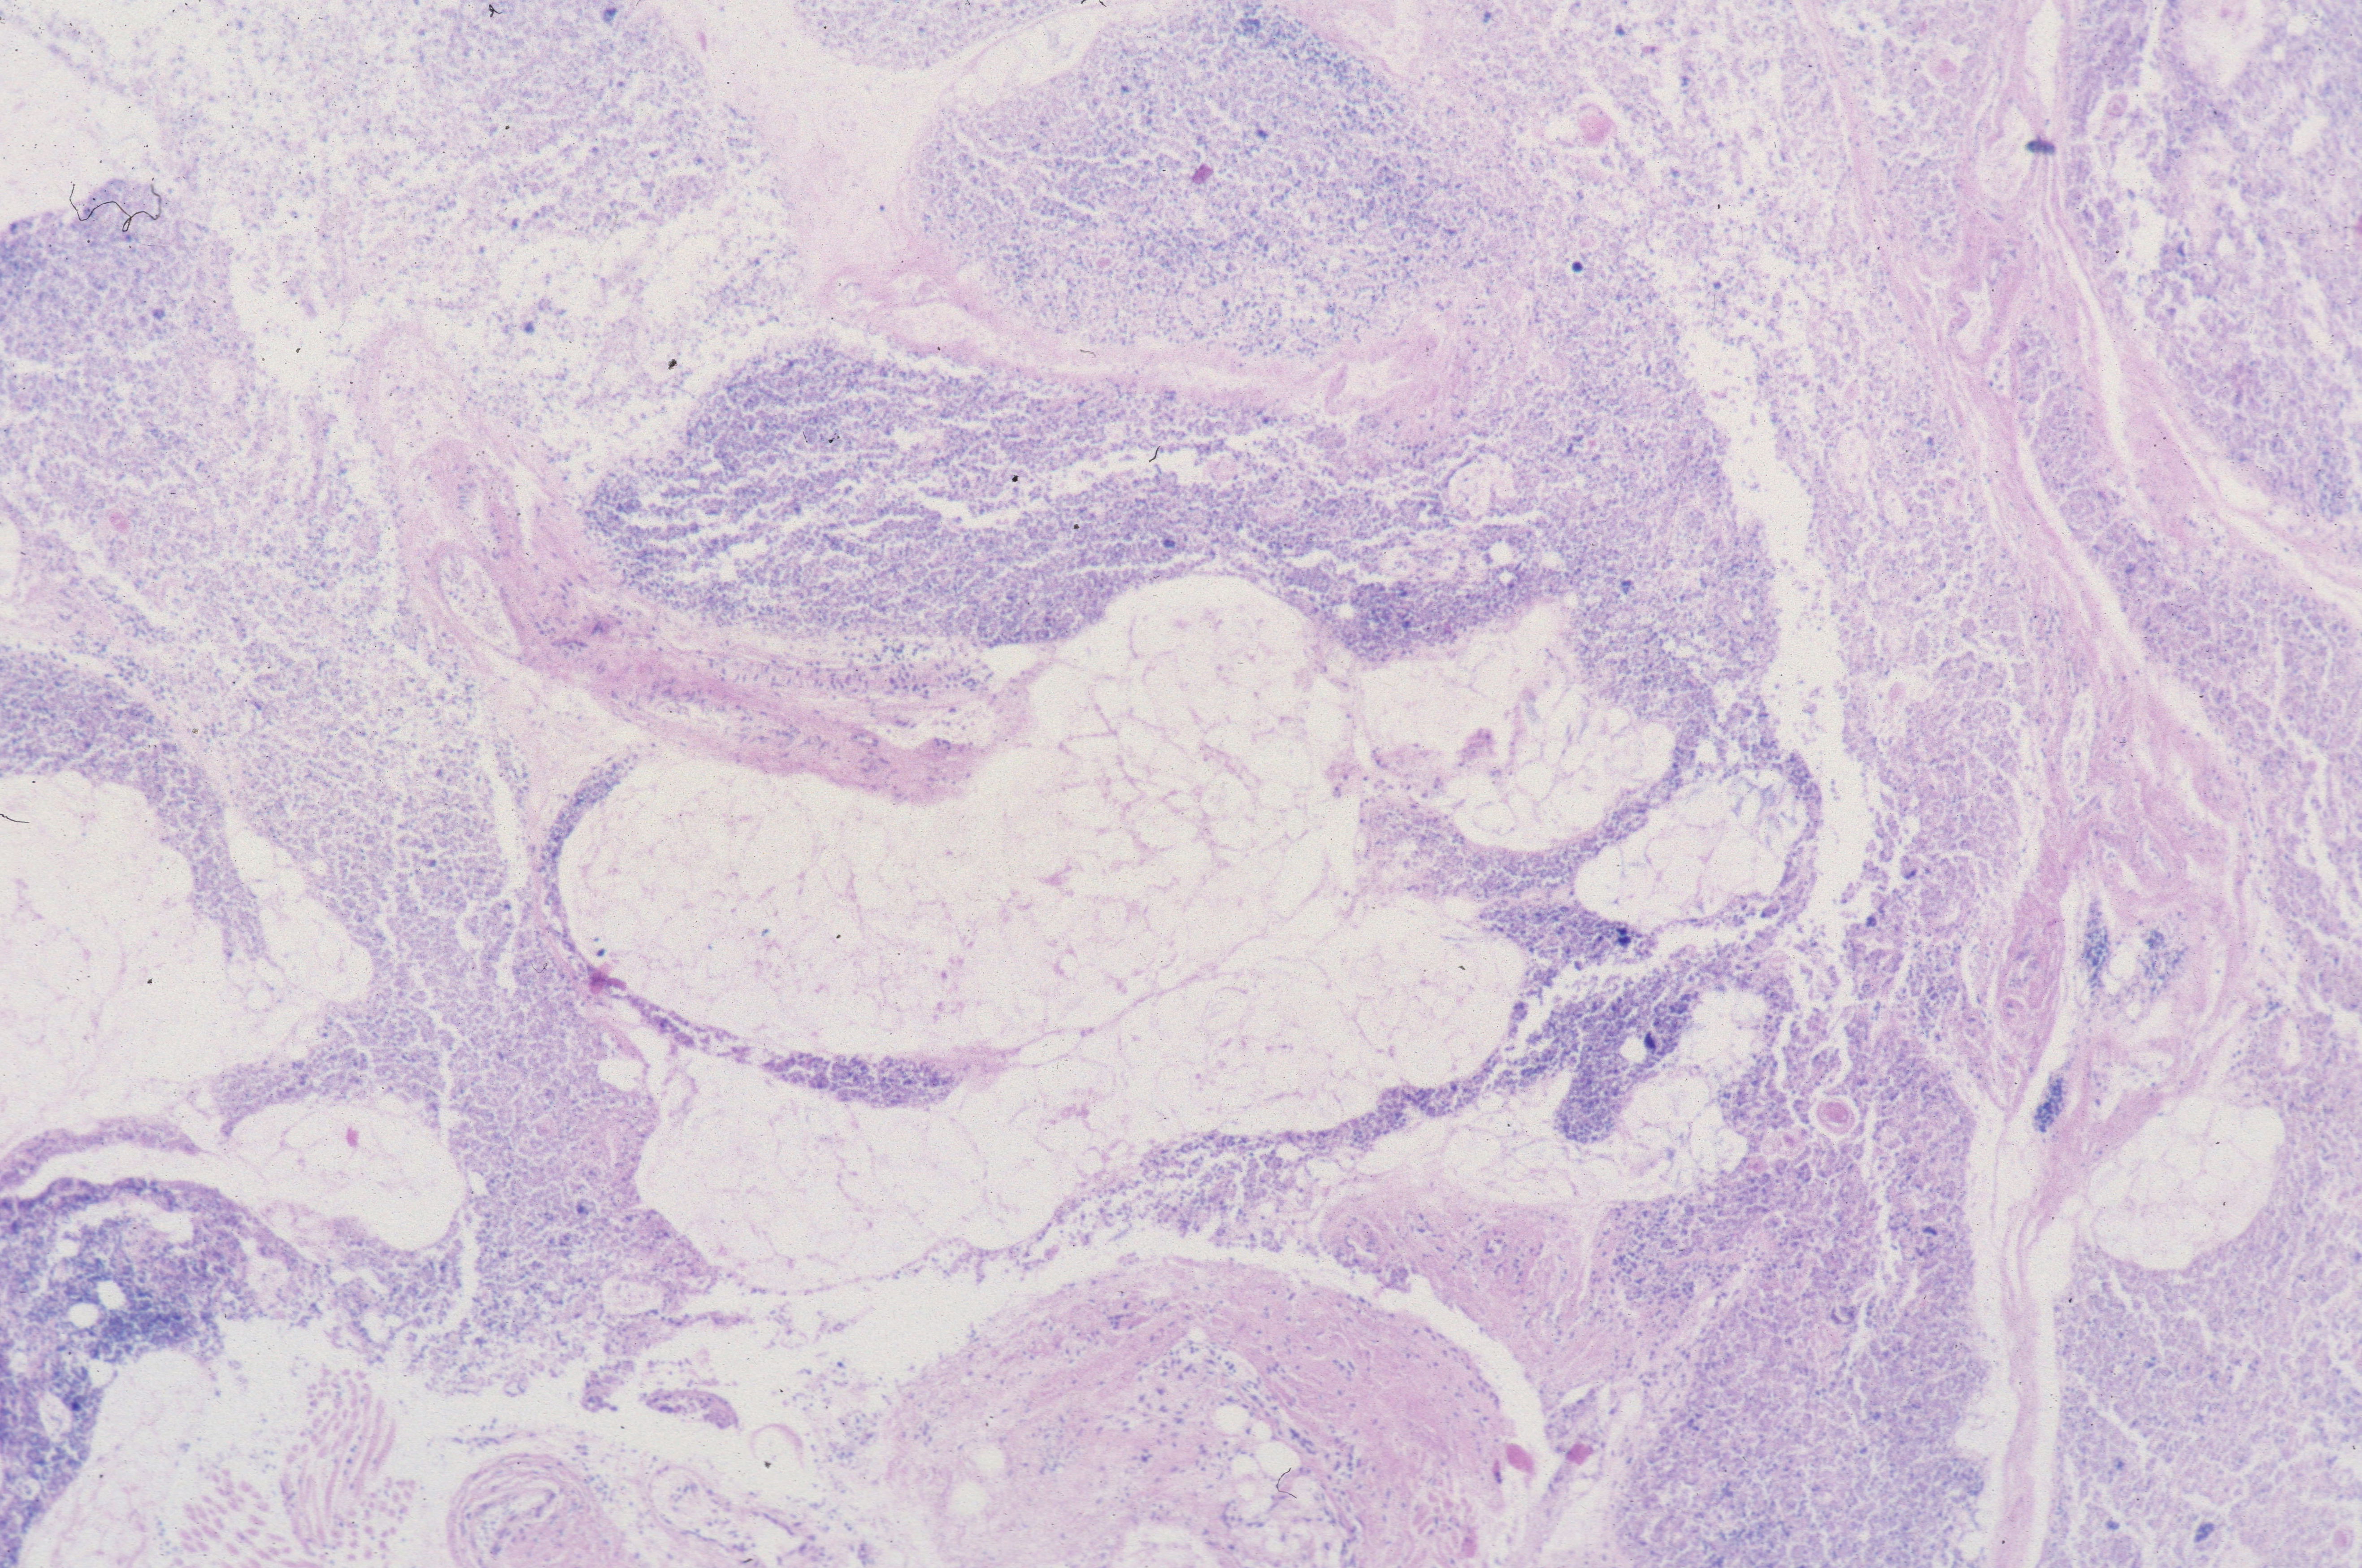

The complexity of thymic changes is demonstrated in a case of a 22 week gestation infant with a week of preterm premature rupture of membranes who was treated with betamethasone (a synthetic corticosteroid that can cross the placenta to the infant and used to promote lung maturation) and antibiotics. The infant survived for three quarters of an hour. The placenta demonstrated choroamnionitis with some fetal inflammation in the superficial chorionic vessels. The autopsy demonstrated complete involution of the thymus, follicular formation in the spleen, and extensive, intense acute pneumonitis with no growth of microorganisms on lung culture. The thymus demonstrated an inverted picture with no cortex and small lymphocytes in the medulla. The cortical rim demonstrated a compact epithelial layer. (Figs 16, 17) This infant had evidence of acute inflammation, and antibody stimulation, making it impossible to assess the changes due to the exogenous steroid.